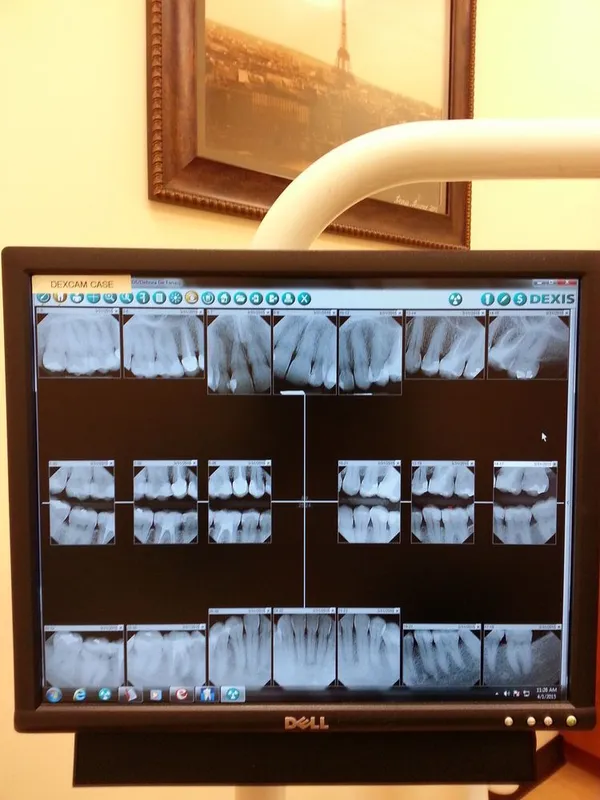

Digital x-rays are quickly becoming adopted by a large percentage of the dental industry. A digital x-ray allows the dentist to take an image of the tooth or teeth and put it into an imaging program. Within this imaging program, there are a number of tools that will allow the dentist to take a very close look at the teeth and surrounding structures with amazing accuracy. As a benefit to the patient, the digital x-ray also provides nearly 80% less radiation than a standard x-ray. This is due to the fact that the digital version of the x-ray is much more sensitive to this radiation and has been specifically designed with the patient in mind.